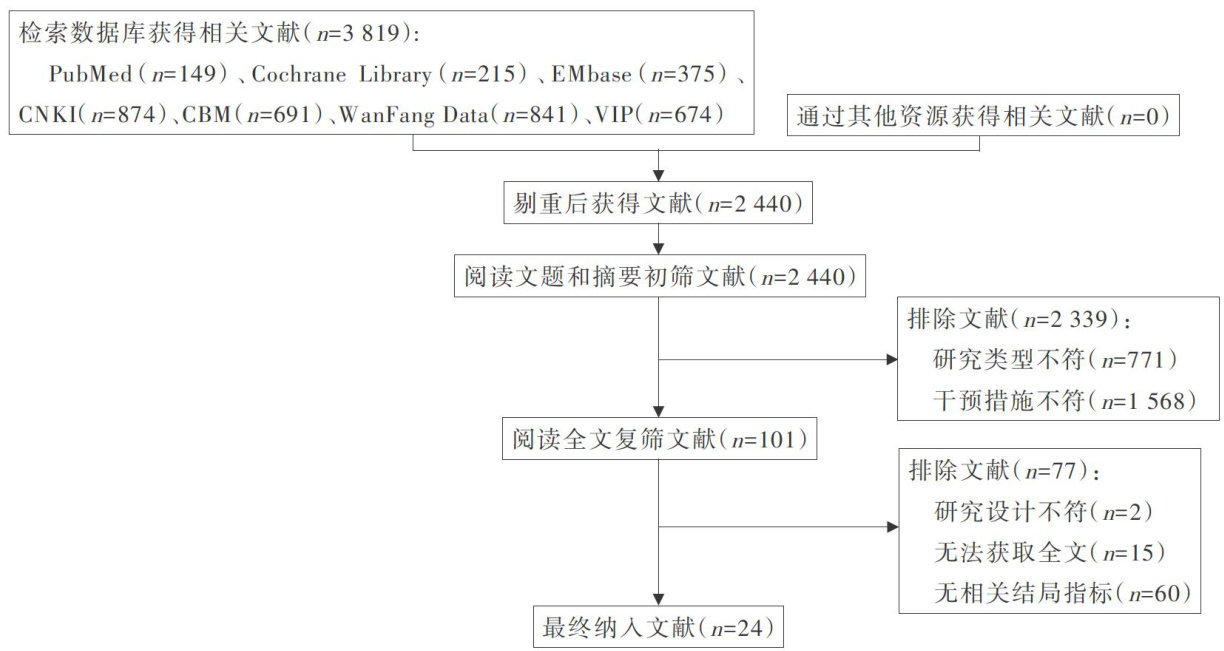

科研论著 | 早期饮水方案在心脏外科术后病人中应用效果的Meta分析

科研论著 | 早期饮水方案在心脏外科术后病人中应用效果的Meta分析